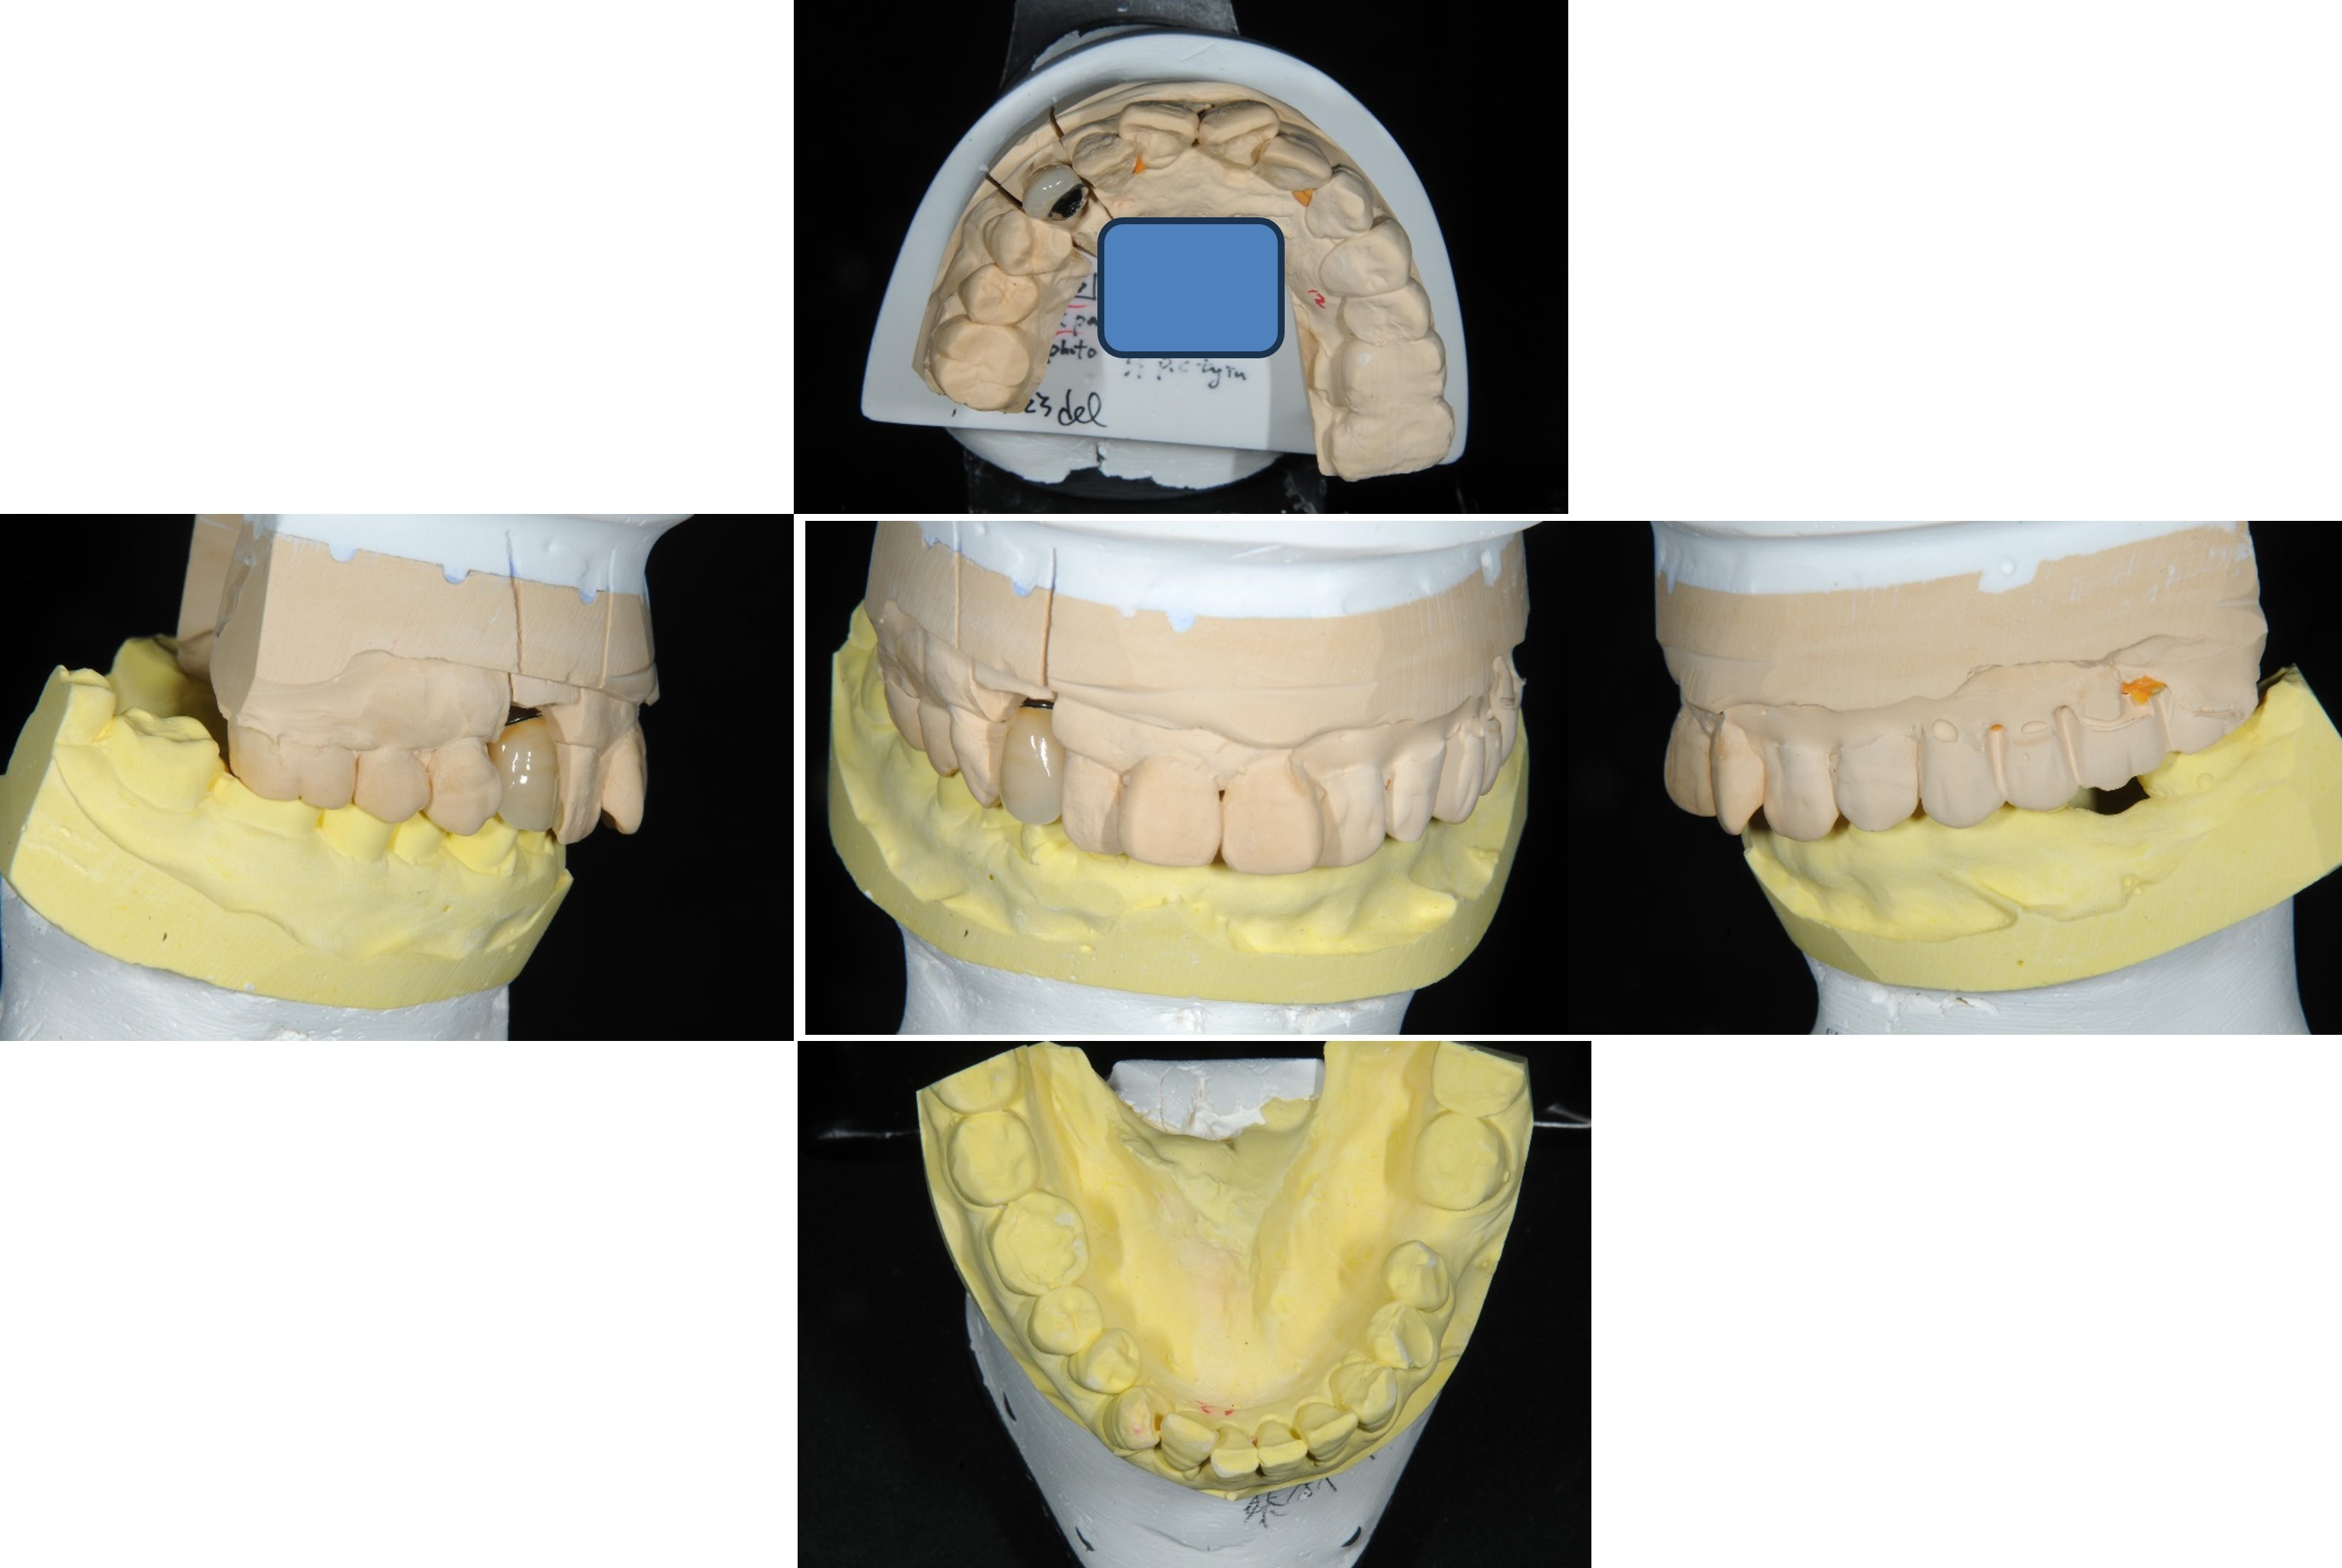

面弓轉移,上咬合器

咬合器上製作瓷牙